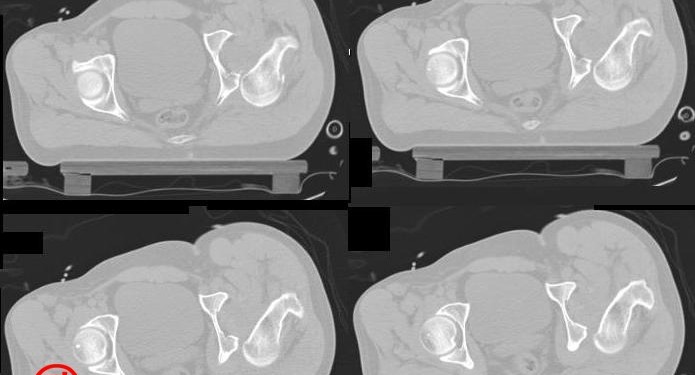

Kalça Çıkığı

Posterior dislokasyon;